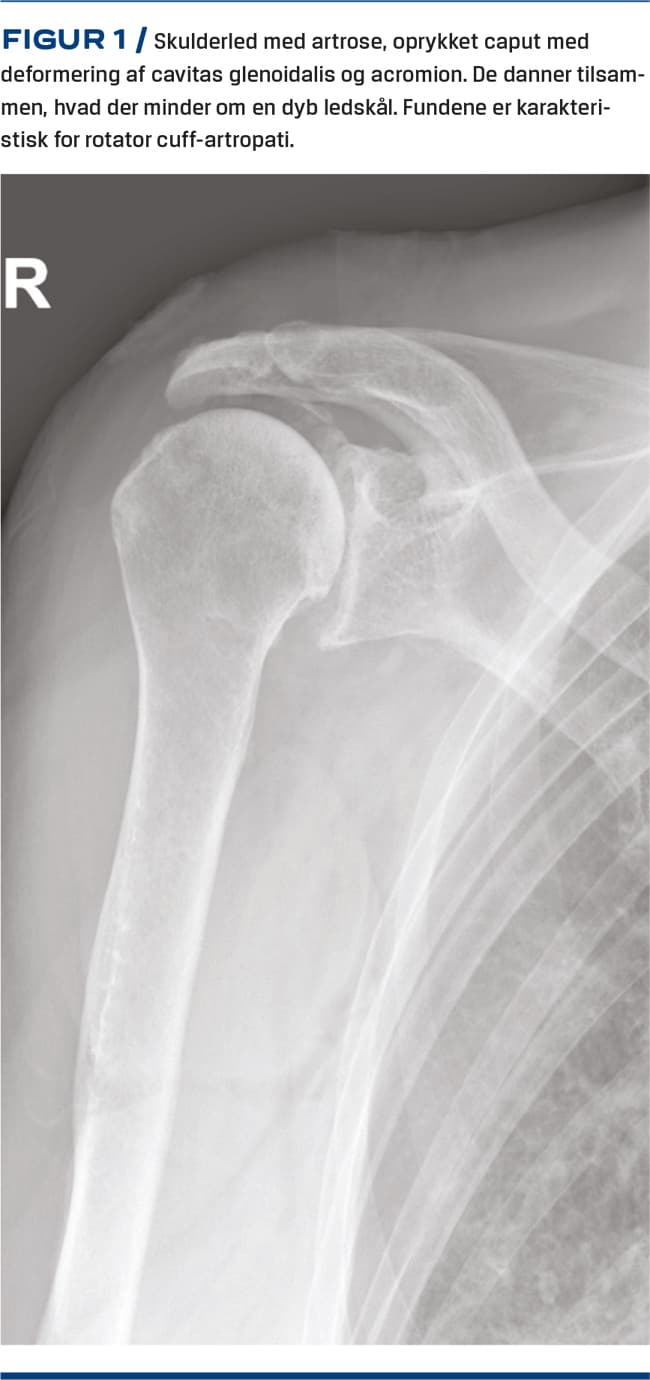

Skulderartrose ses både primært og sekundært i forbindelse med fraktur, ustabilitet eller slid i rotator cuff-senerne. Ved samtidig artrose og rotator cuff-destruktion benævnes tilstanden rotator cuff-artropati (Figur 1). Prævalensen af artrose i skulderleddet er ca. 20% efter 80-årsalderen [1]. Patienter, der opereres med en skulderalloplastik, monitoreres af Dansk Skulderalloplastik Register (DSR) [2]. Her er der påvist en stigning i antallet af alloplastikker, som er indsat pga. artrose eller rotator cuff-artropati, fra 356 i 2008 til 836 i 2019. Årsagen til stigningen er ukendt, men kan skyldes en stigende forekomst af svære tilfælde, bedre behandlingsmuligheder, bedre kendskab til disse eller indikationsskred.

Objektivt kan der være nedsat bevægelighed og skurren. Rotator cuff-funktionen vurderes på baggrund af muskelatrofi og nedsat styrke (Figur 2).